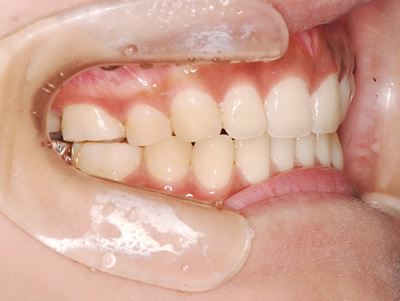

上顎の劣成長 (成長不足) による反対咬合で、上顎は拡大装置と上顎前方牽引装置を併用し前方方向への成長を促して前歯の咬み合わせを改善した後に、上下顎の前歯をマルチブラケット装置で並べました。治療の期間は2年でした。

初診時

1期治療終了時

2期治療終了時

| 費用の目安 | 440,000(税込) | |

| 治療期間の目安 | 2年 | |